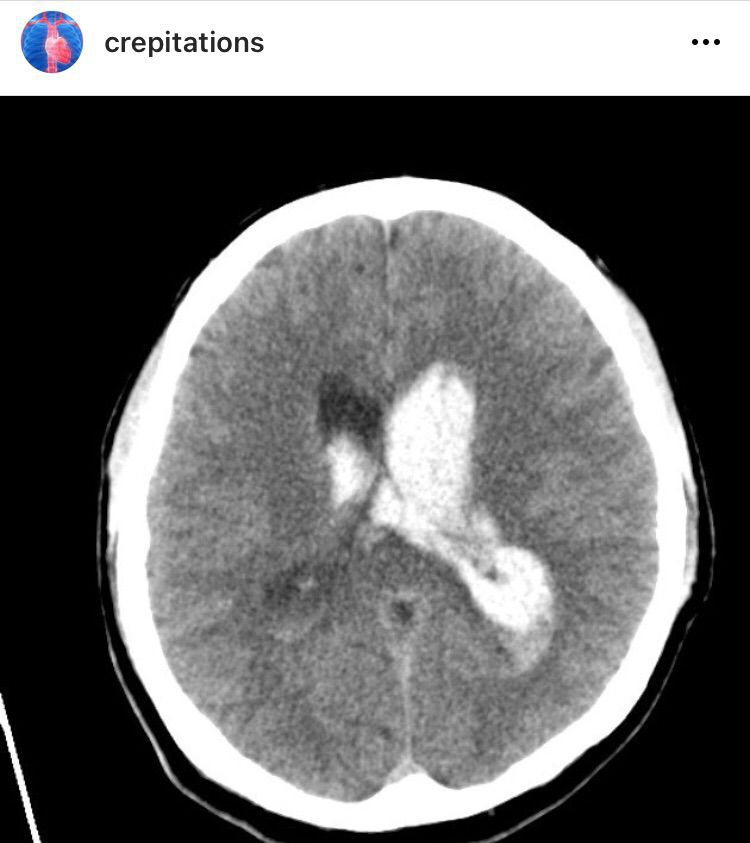

Primary Intraventricular Hemorrhage (CT)

Brain

Ct

Hemorrhage

Cranium

Computedtomography